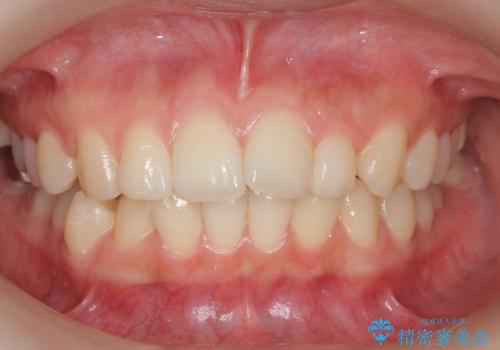

上唇小帯切除

担当医 青山卓弘